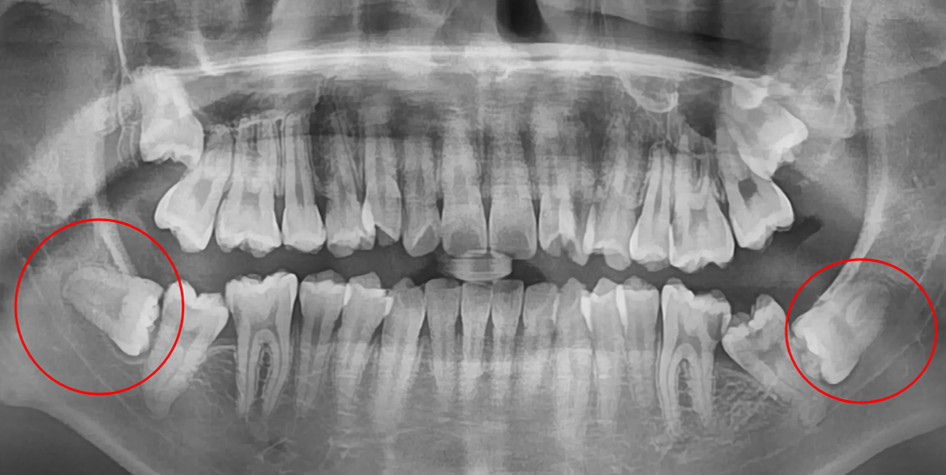

발치 전

사랑니 발치 후

20대 여성 환자분으로, 사랑니가 4개 있는 상태로 불편감이 있어 모두 발치를 원하셨습니다.

약 2주 후 출국 예정으로 불가피하게 당일 4개를 모두 발치를 해야 했었습니다. * 일반적으로는 사랑니 4개를 발치 할 때 왼쪽, 오른쪽으로 나누어 최소 1-2주 간 텀을 두고 발치를 합니다.